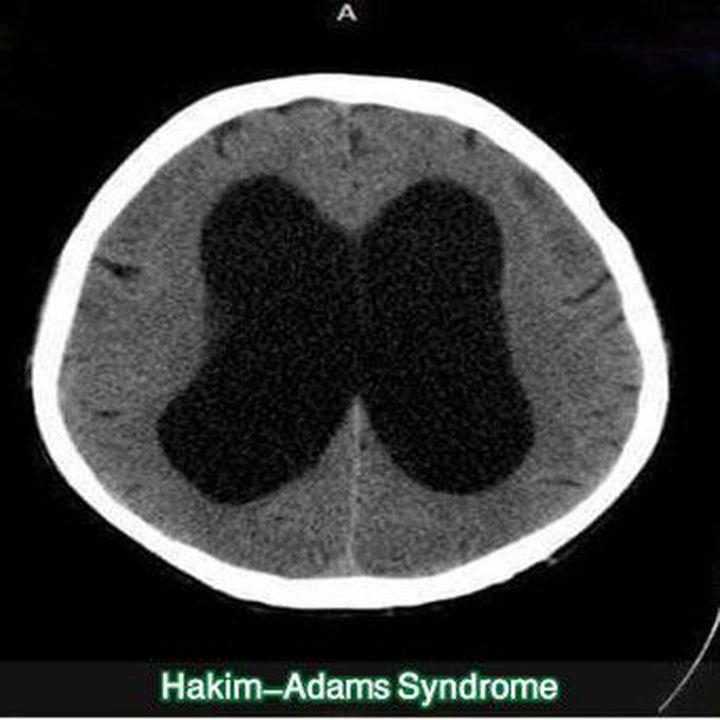

Hydrocephalus without high brain pressure ( old patients ) 1 Instability of walking : * short slow steps * wide base of support * instability of position * tendency to fall back 2 Mismanagement of Misrata 3 Dementia * decline of mental functions of the subcortical model Treatment : Peritoneal - Cerebral Valve